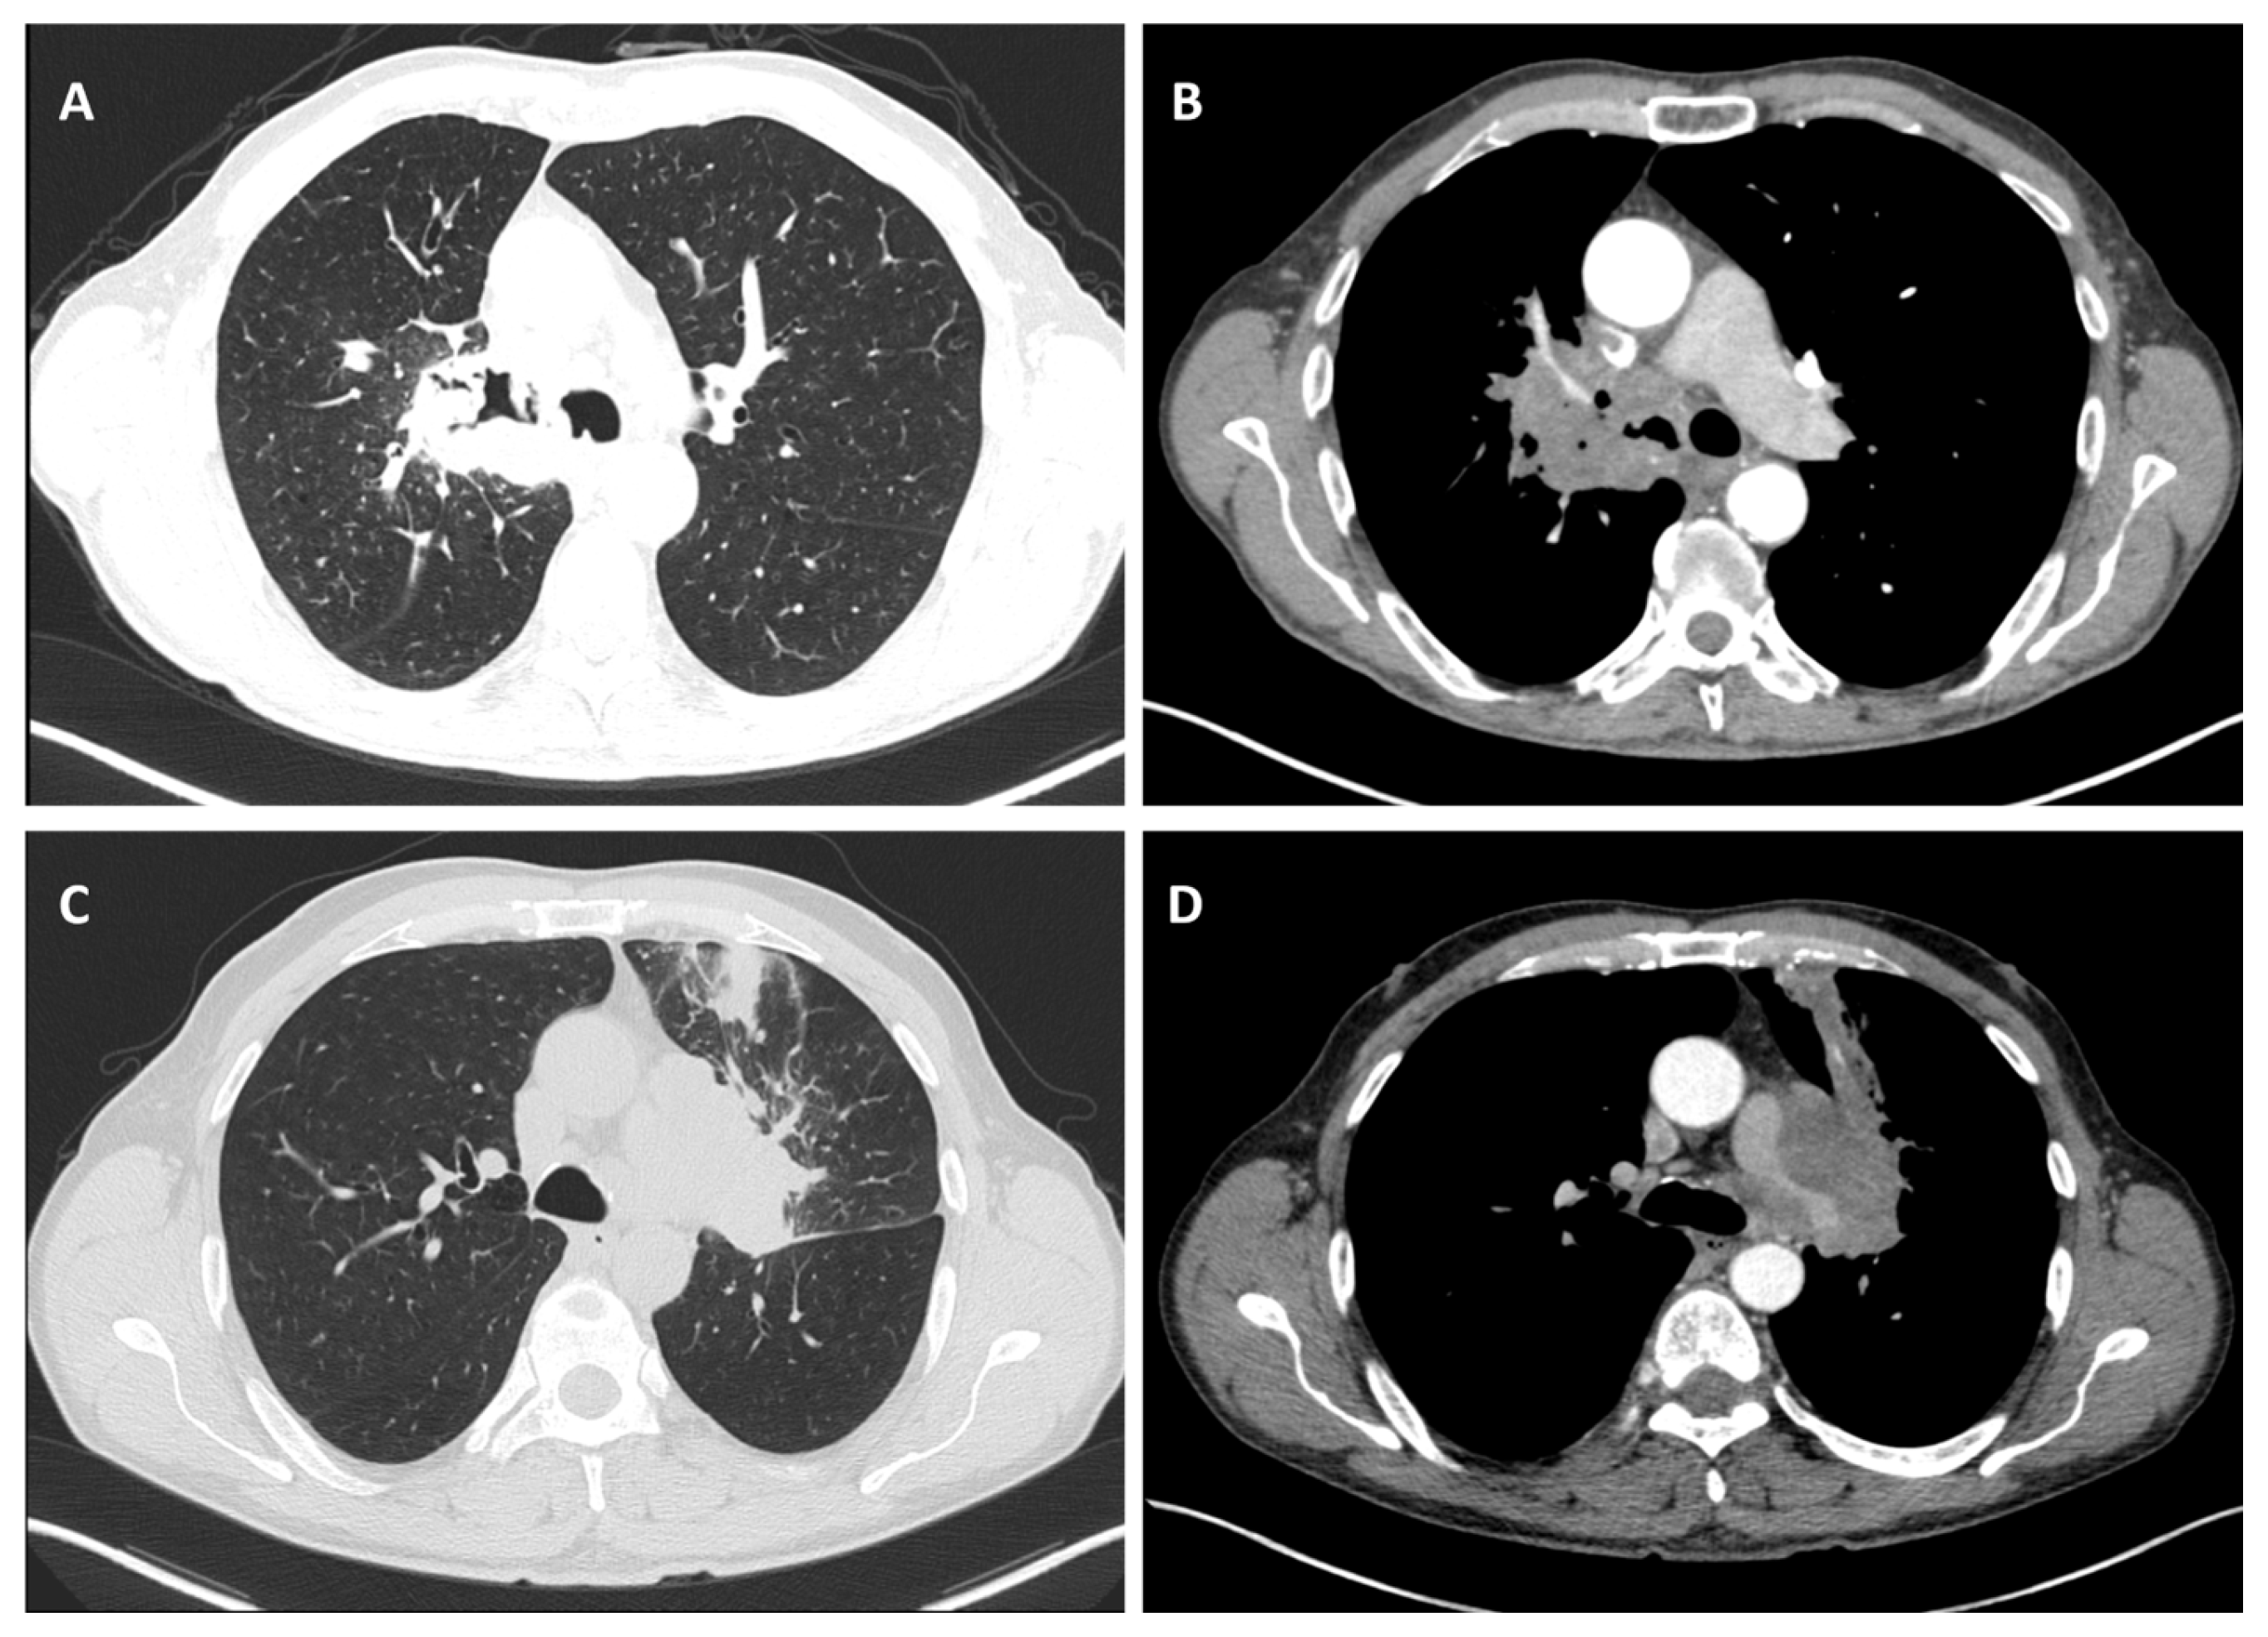

3.2.2. Location

3.2.5. Local Invasion

3.2.6. Other Features—Bronchial Obstruction and Vascular Bundle Thickening

3.2.7. Lymph Node Involvement